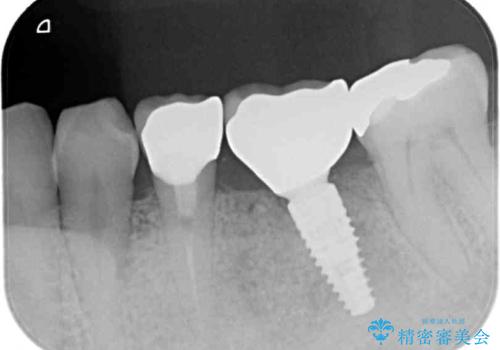

また、上顎の欠損部位にはインプラント治療を行うこととしました。

改めて診療を行ったところ、歯根破折が認められ、抜歯後にインプラント治療を行うこととしました。

下顎大臼歯の抜歯決断までに時間がかかったため、治療期間はやや長くなりましたが、安定した咬み合わせとなり、痛みもなく安心して噛めるようになりました。